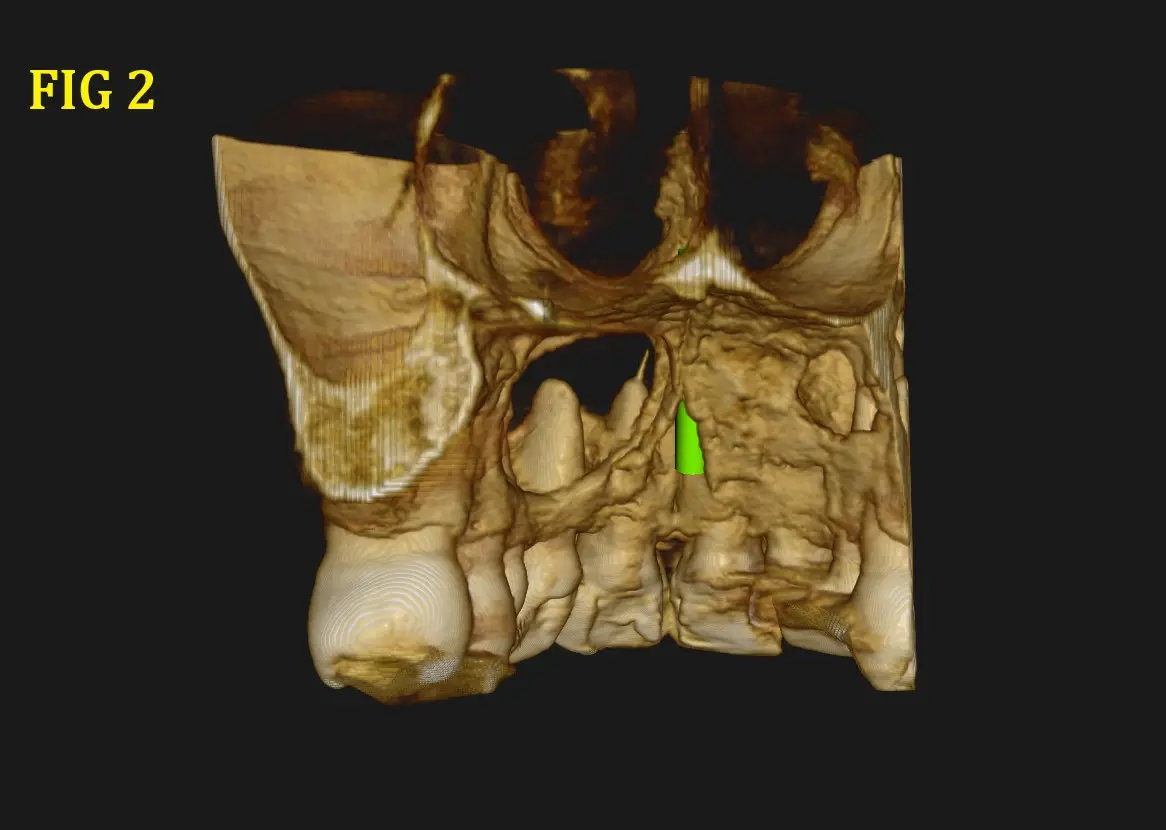

Al realizarle la tomografía se observó una imagen hipodensa (Fig. 1 y 2) proveniente de la pieza dental 21, pieza en la que fue realizada un tratamiento de conducto, donde se llega a observar una sobre obturación (Overfilling) (Fig. 3 y 4), el material hiperdenso se observa sobresalir del ápice radicular sobrepasando el limite CDC (conección Dentino-Cementaria) , generando el quiste periapical. ( Fig. 5). El quiste va generando presion a las piezas adyacentes y se extiende desde pieza dental 21 a 23 inclusive.

Se describe la tipica imagen expansiva sobre los tejidos scircundantes, tipo globo con agua, que tiene limites bien definidos, aunque por su tamaño y posibles reagudizaciones en algunas zonas se encuentra ausente o cueste distinguirlo, provocando ensanchamiento de las tablas libres y adelgazamiento